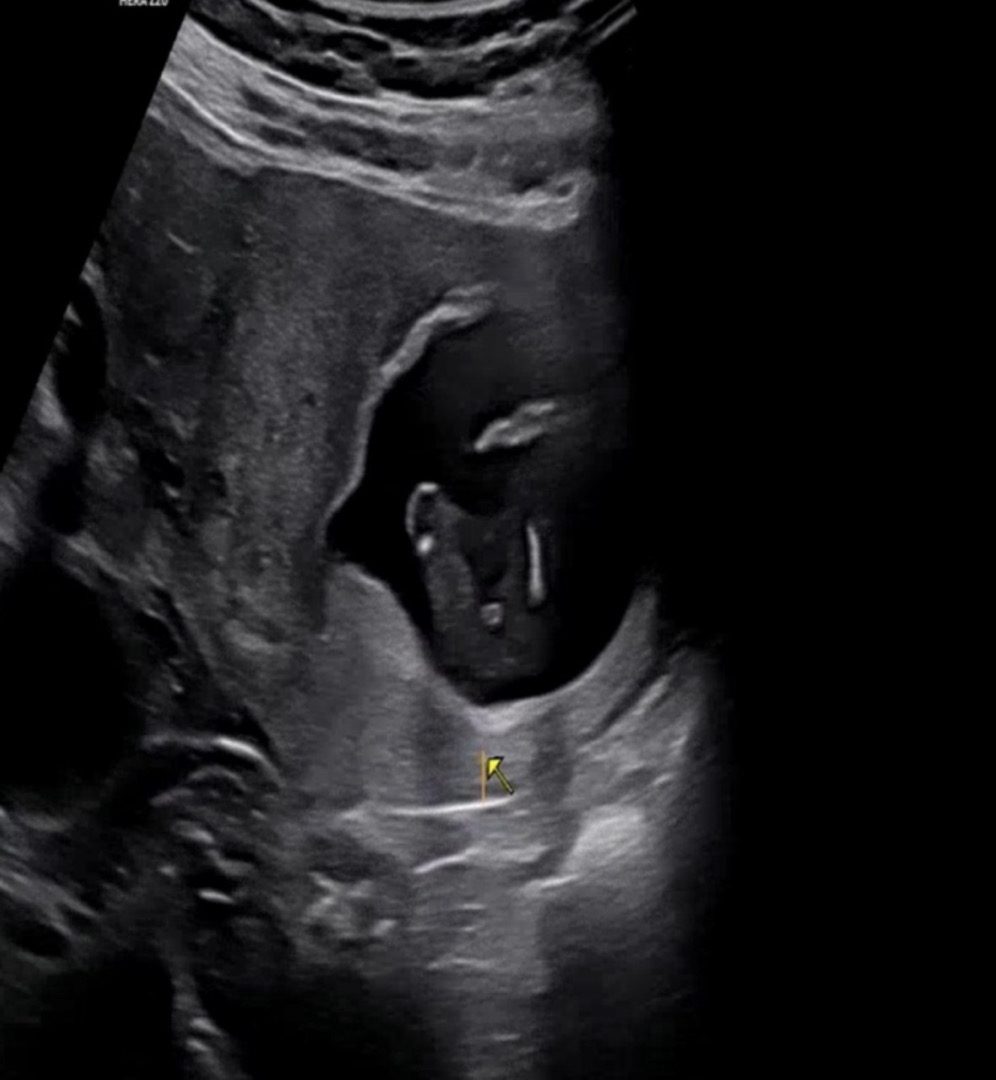

13주에 찍은 초음파인데 다리사이에 탯줄일까요 고추일까요...?